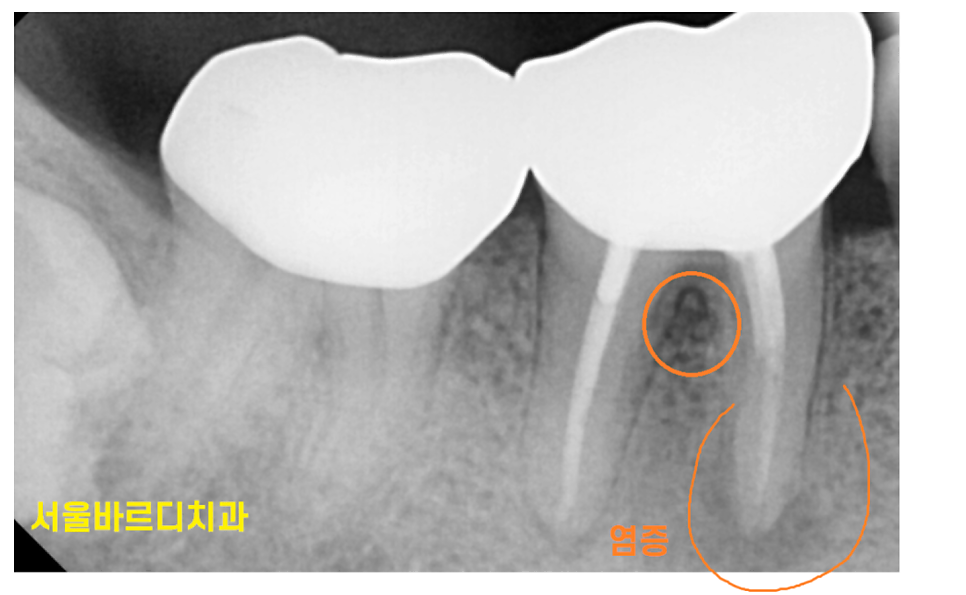

대표적인 원인으로는 뿌리 끝 염증이 있습니다.

이미 신경치료를 받았던 치아이거나

치아 뿌리 끝에 염증이 생기고 고름이 찰 수 있습니다.

240127 풍치와 뿌리 끝 염증이 동시에 있는 환자분

이 경우 겉으로는 멀쩡해 보여도 내부는 심각한 상태일 수 있죠.

풍치와 뿌리 끝 염증이 동시에 있을 수도 있습니다.